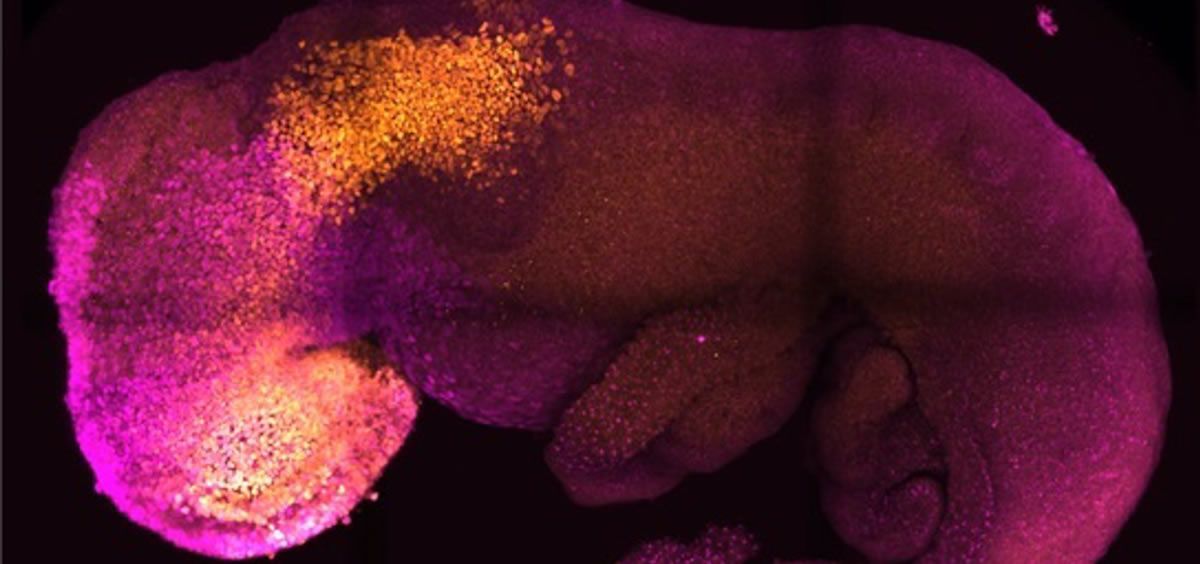

Las células madre se autoorganizaron en estructuras que progresaron a través de las sucesivas etapas de desarrollo hasta tener corazones que latían y las bases del cerebro, así como el saco vitelino donde el embrión se desarrolla y obtiene los nutrientes en sus primeras semanas. A diferencia de otros embriones sintéticos, los modelos desarrollados por Cambridge alcanzaron el punto en el que todo el cerebro, incluida la parte anterior, comenzó a desarrollarse. Se trata de un punto de desarrollo más avanzado del que se ha alcanzado en cualquier otro modelo derivado de células madre.

A diferencia de otros embriones sintéticos, los modelos desarrollados por Cambridge alcanzaron el punto en el que todo el cerebro, incluida la parte anterior, comenzó a desarrollarse.

"Nuestro modelo de embrión de ratón no sólo desarrolla un cerebro, sino también un corazón que late, y todos los componentes que conforman el cuerpo --afirma Zernicka-Goetz, catedrática de Desarrollo de Mamíferos y Biología de Células Madre del Departamento de Fisiología, Desarrollo y Neurociencia de Cambridge--. Es increíble que hayamos llegado tan lejos".

Un gran avance del estudio es la capacidad de generar todo el cerebro, en particular la parte anterior, que ha sido un objetivo importante en el desarrollo de embriones sintéticos. Esto funciona en el sistema de Zernicka-Goetz porque esta parte del cerebro requiere señales de uno de los tejidos extraembrionarios para poder desarrollarse. El equipo pensó que esto podría tener lugar a partir de sus estudios de 2018 y 2021, que utilizaron las mismas células componentes para desarrollarse en embriones en una fase ligeramente anterior. Ahora, al llevar el desarrollo un día más allá, pueden afirmar definitivamente que su modelo es el primero que señala el desarrollo de la parte anterior, y de hecho de todo el cerebro.

"Esto abre nuevas posibilidades para estudiar los mecanismos del neurodesarrollo en un modelo experimental --subraya Zernicka-Goetz--. De hecho, en el artículo demostramos la prueba de este principio eliminando un gen que ya se sabe que es esencial para la formación del tubo neural, precursor del sistema nervioso, y para el desarrollo del cerebro y los ojos. En ausencia de este gen, los embriones sintéticos muestran exactamente los defectos conocidos en el desarrollo del cerebro como en un animal portador de esta mutación. Esto significa que podemos empezar a aplicar este tipo de enfoque a los muchos genes con función desconocida en el desarrollo del cerebro".